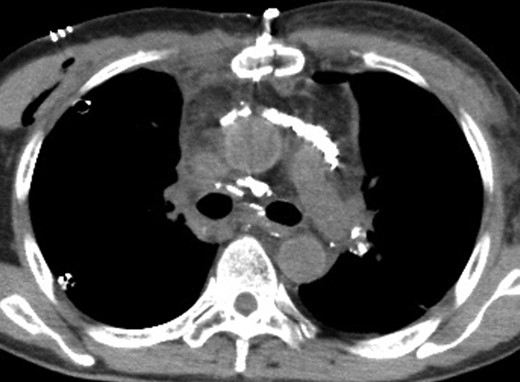

A 67-year-old man was referred to our hospital after transbronchial biopsy confirmed a diagnosis of non-small cell lung cancer. His physical examination findings and laboratory data were unremarkable. CT revealed a right upper lobe mass (diameter, 4.1 cm) in the apical portion; and thus, invasion of the right subclavian artery was suspected. On clinical staging, the tumor was T4N0M0, Stage IIIA. He underwent right upper lobectomy and mediastinal lymph node dissection via median sternotomy. Complete resection was achieved without concomitant resection of the right subclavian artery. The histological diagnosis was squamous cell carcinoma (pT3aN0M0, Stage IIB). Two drainage tubes were placed in the right thoracic cavity, and a total milky fluid volume of 2000 ml was drained on postoperative day (POD) 2. The volume of chylous drainage did not reduce with total parenteral nutrition. On POD 4, right-sided video-assisted thoracic surgery was performed 1 hour after intake of ice cream, to identify the site of chylous leakage. On intraoperative observation, multiple leakage sites were noted between the trachea and superior vena cava, and these sites were clipped and sealed with fibrin glue. However, the thoracic duct could not be identified in the right posterior mediastinum. After this surgical procedure, the volume of chylous drainage did not decrease. In addition, on POD 5 the patient complained of dyspnea. A chest X-ray revealed left pleural effusion, and a drainage tube was inserted into the left pleural cavity. LAG was performed to identify the leakage site, and the total amount of drained effusion from both sides was 3200 ml/day on POD 6 (2 days after the reoperation). The right inguinal lymph node was punctured with a 23-gauge needle under ultrasound guidance, and a total lipiodol volume of 7 ml was slowly injected under fluoroscopic guidance. CT after LAG revealed that the thoracic duct was located on the left side (Fig. 1). However, a day after LAG, the leakage site could not be clearly identified. Additionally, CT showed accumulation of lipiodol at the anterior mediastinum, which suggested the presence of chylous leakage from the thoracic duct tributaries in the anterior mediastinum (Fig. 2). Bilateral pleural effusion gradually decreased after LAG, and a low-fat diet was started on POD 20. The right and left chest drainage tubes were removed on POD 21 and POD 28, respectively. The patient was eventually discharged 30 days after the first surgery (23 days after LAG). CT performed 2 months after LAG revealed lipiodol retention in the thoracic duct and mediastinum. The patient remains asymptomatic without pleural effusion at 6 months after discharge.

A CT image 1 day after lymphangiography shows lipiodol accumulation in the anterior mediastinum and between the bilateral main bronchi and aorta.